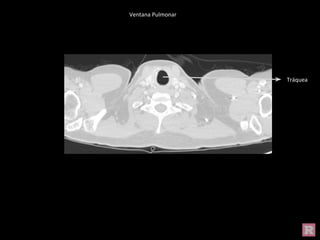

Ventana Pulmonar

Tráquea